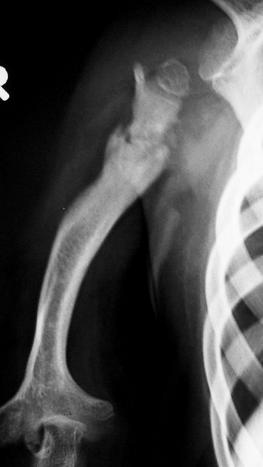

Pathological #!

Patient is 8 years old now.

X-ray showing deformed Humerus with shoulder functions impaired